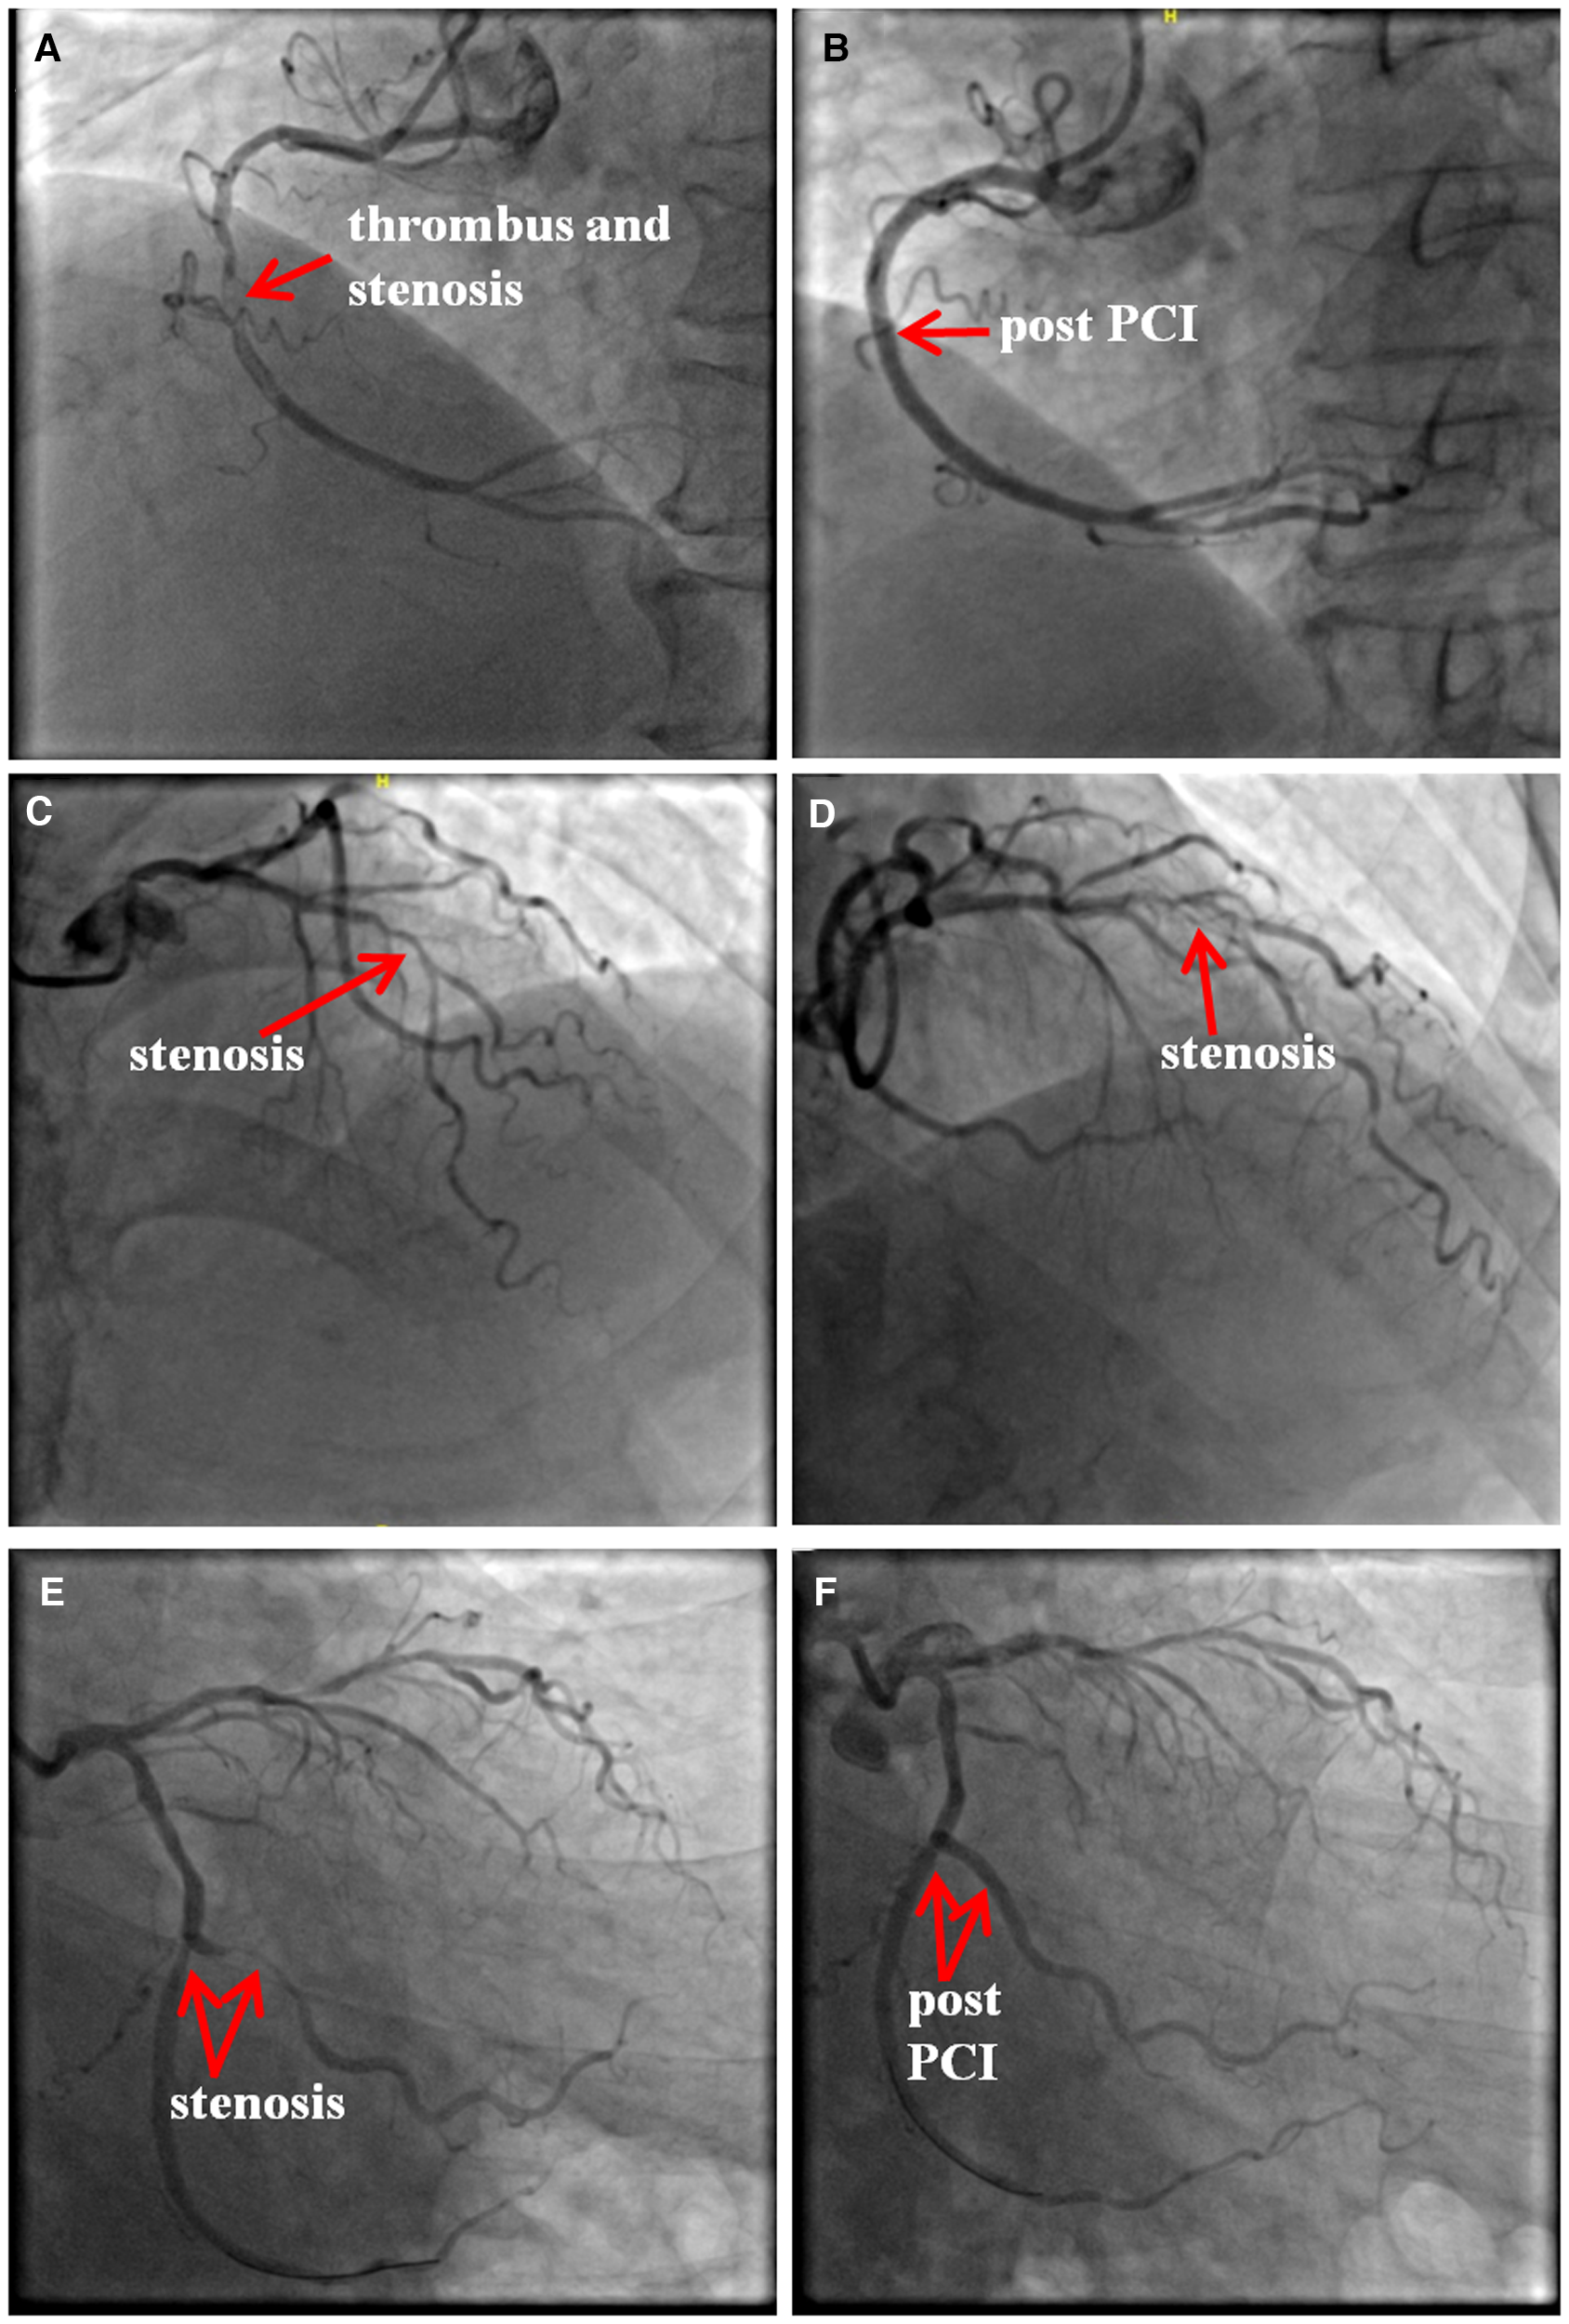

On admission, the electrocardiogram (ECG) showed that ST segments were elevated in leads II, III and avF, with reciprocal depression in leads I and avL (Figure 1A). Transthoracic echocardiography revealed hypokinesia on the inferior and posterior walls, with a left ventricular ejection fraction of 54%. The CAG revealed 95% stenosis in the right coronary artery (RCA) with thrombotic shadow locally, 80% stenosis in the left anterior descending coronary artery, 70%–80% stenosis in the distal left circumflex coronary artery (d-LCX), and 80%–90% stenosis in the obtuse marginal branch (OM) (Figures 2A,2C–E).

Figure 2

The results of coronary angiography. There was 95% stenosis in the right coronary artery (RCA) with a local thrombotic shadow (A), and two drug eluting stents (DES, Firebird 3.0 × 29 mm, Firebird 3.5 × 33 mm) were implanted into the RCA. (B) There was 80% stenosis in the left anterior descending coronary artery (C,D). There was 80%–90% stenosis in the obtuse marginal branch (OM) and 70%–80% stenosis in the distal LCX (d-LCX) (E), and a DES (Promus Element 2.25 × 20 mm) and a drug-coated balloon (Vesselin 3.0 × 16 mm) were implanted in the OM and d-LCX, respectively. (F) PCI, percutaneous coronary intervention.

Combined with the ECG result, RCA was considered as the culprit vessel. Therefore, thrombus aspiration was performed, and two drug-eluting stents (DES, Firebird 3.0 × 29 mm, Firebird 3.5 × 33 mm) were implanted into the RCA (Figure 2B). This was accompanied by oral drugs for secondary prevention (aspirin, ticagrelor, atorvastatin, metoprolol). Subsequently, the ECG showed pathological Q waves in the inferior leads with ST segment recovery (Figure 1B). Before discharge, a DES (Promus Element 2.25 × 20 mm) and a drug-coated balloon (Vesselin 3.0 × 16 mm) were implanted into the OM and d-LCX, respectively (Figure 2F). A week later, the abnormal cardiac injury markers were relieved. The patient was discharged from the hospital in good condition. Furthermore, at the 1-month and 6-month follow-up visits after discharge, he was doing well with no symptoms or abnormalities of cardiac markers. A schematic diagram showing the timeline from vaccination to the onset of AMI up until patient discharge was showed in Figure 3.